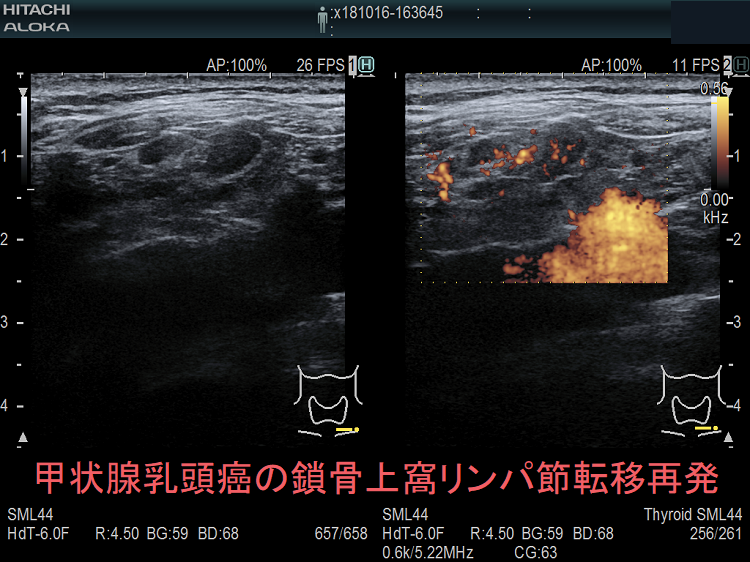

甲状腺乳頭癌の鎖骨上窩リンパ節転移再発

甲状腺乳頭癌鎖骨上窩リンパ節転移再発

ケース①

甲状腺乳頭癌の鎖骨上窩リンパ節転移再発 超音波(エコー)画像

鎖骨上窩は予防的リンパ節郭清(前頚部リンパ節郭清)の範囲外につき、術後リンパ節再発のピットフォールとなります(意外とよく見つかります)。

甲状腺乳頭癌が左鎖骨上窩リンパ節に転移して再発すると、左静脈角から血流に乗って全身へ運ばれ、遠隔転移を来します。左鎖骨上窩の転移リンパ節をウィルヒョウリンパ節、左鎖骨上窩リンパ節転移をウィルヒョウ転移と言います。

甲状腺乳頭癌 左鎖骨上窩リンパ節転移再発

甲状腺乳頭癌 左鎖骨上窩リンパ節転移再発;いびつな形で、リンパ門は消失。内部に異常な走行の血管を認め、血流豊富。

ケース②

甲状腺乳頭癌 鎖骨上窩リンパ節転移 超音波(エコー)画像

甲状腺乳頭癌 左鎖骨上窩リンパ節転移 超音波(エコー)画像;いびつな形で、周囲との境界が一部不明瞭化して浸潤が疑われる。リンパ門は消失し、砂粒状石灰化が著明

甲状腺乳頭癌 鎖骨上窩リンパ節転移 超音波(エコー)画像 ドプラーモード

甲状腺乳頭癌 左鎖骨上窩リンパ節転移 超音波(エコー)画像 ドプラーモード;内部に異常な走行の血管を認め、血流豊富。

甲状腺乳頭癌 鎖骨上窩リンパ節転移 超音波(エコー)画像 ドプラーモード2

甲状腺乳頭癌 左鎖骨上窩リンパ節転移 超音波(エコー)画像 ドプラーモード;いびつな形のリンパ節内部に異常な走行の血管を認め、血流豊富。